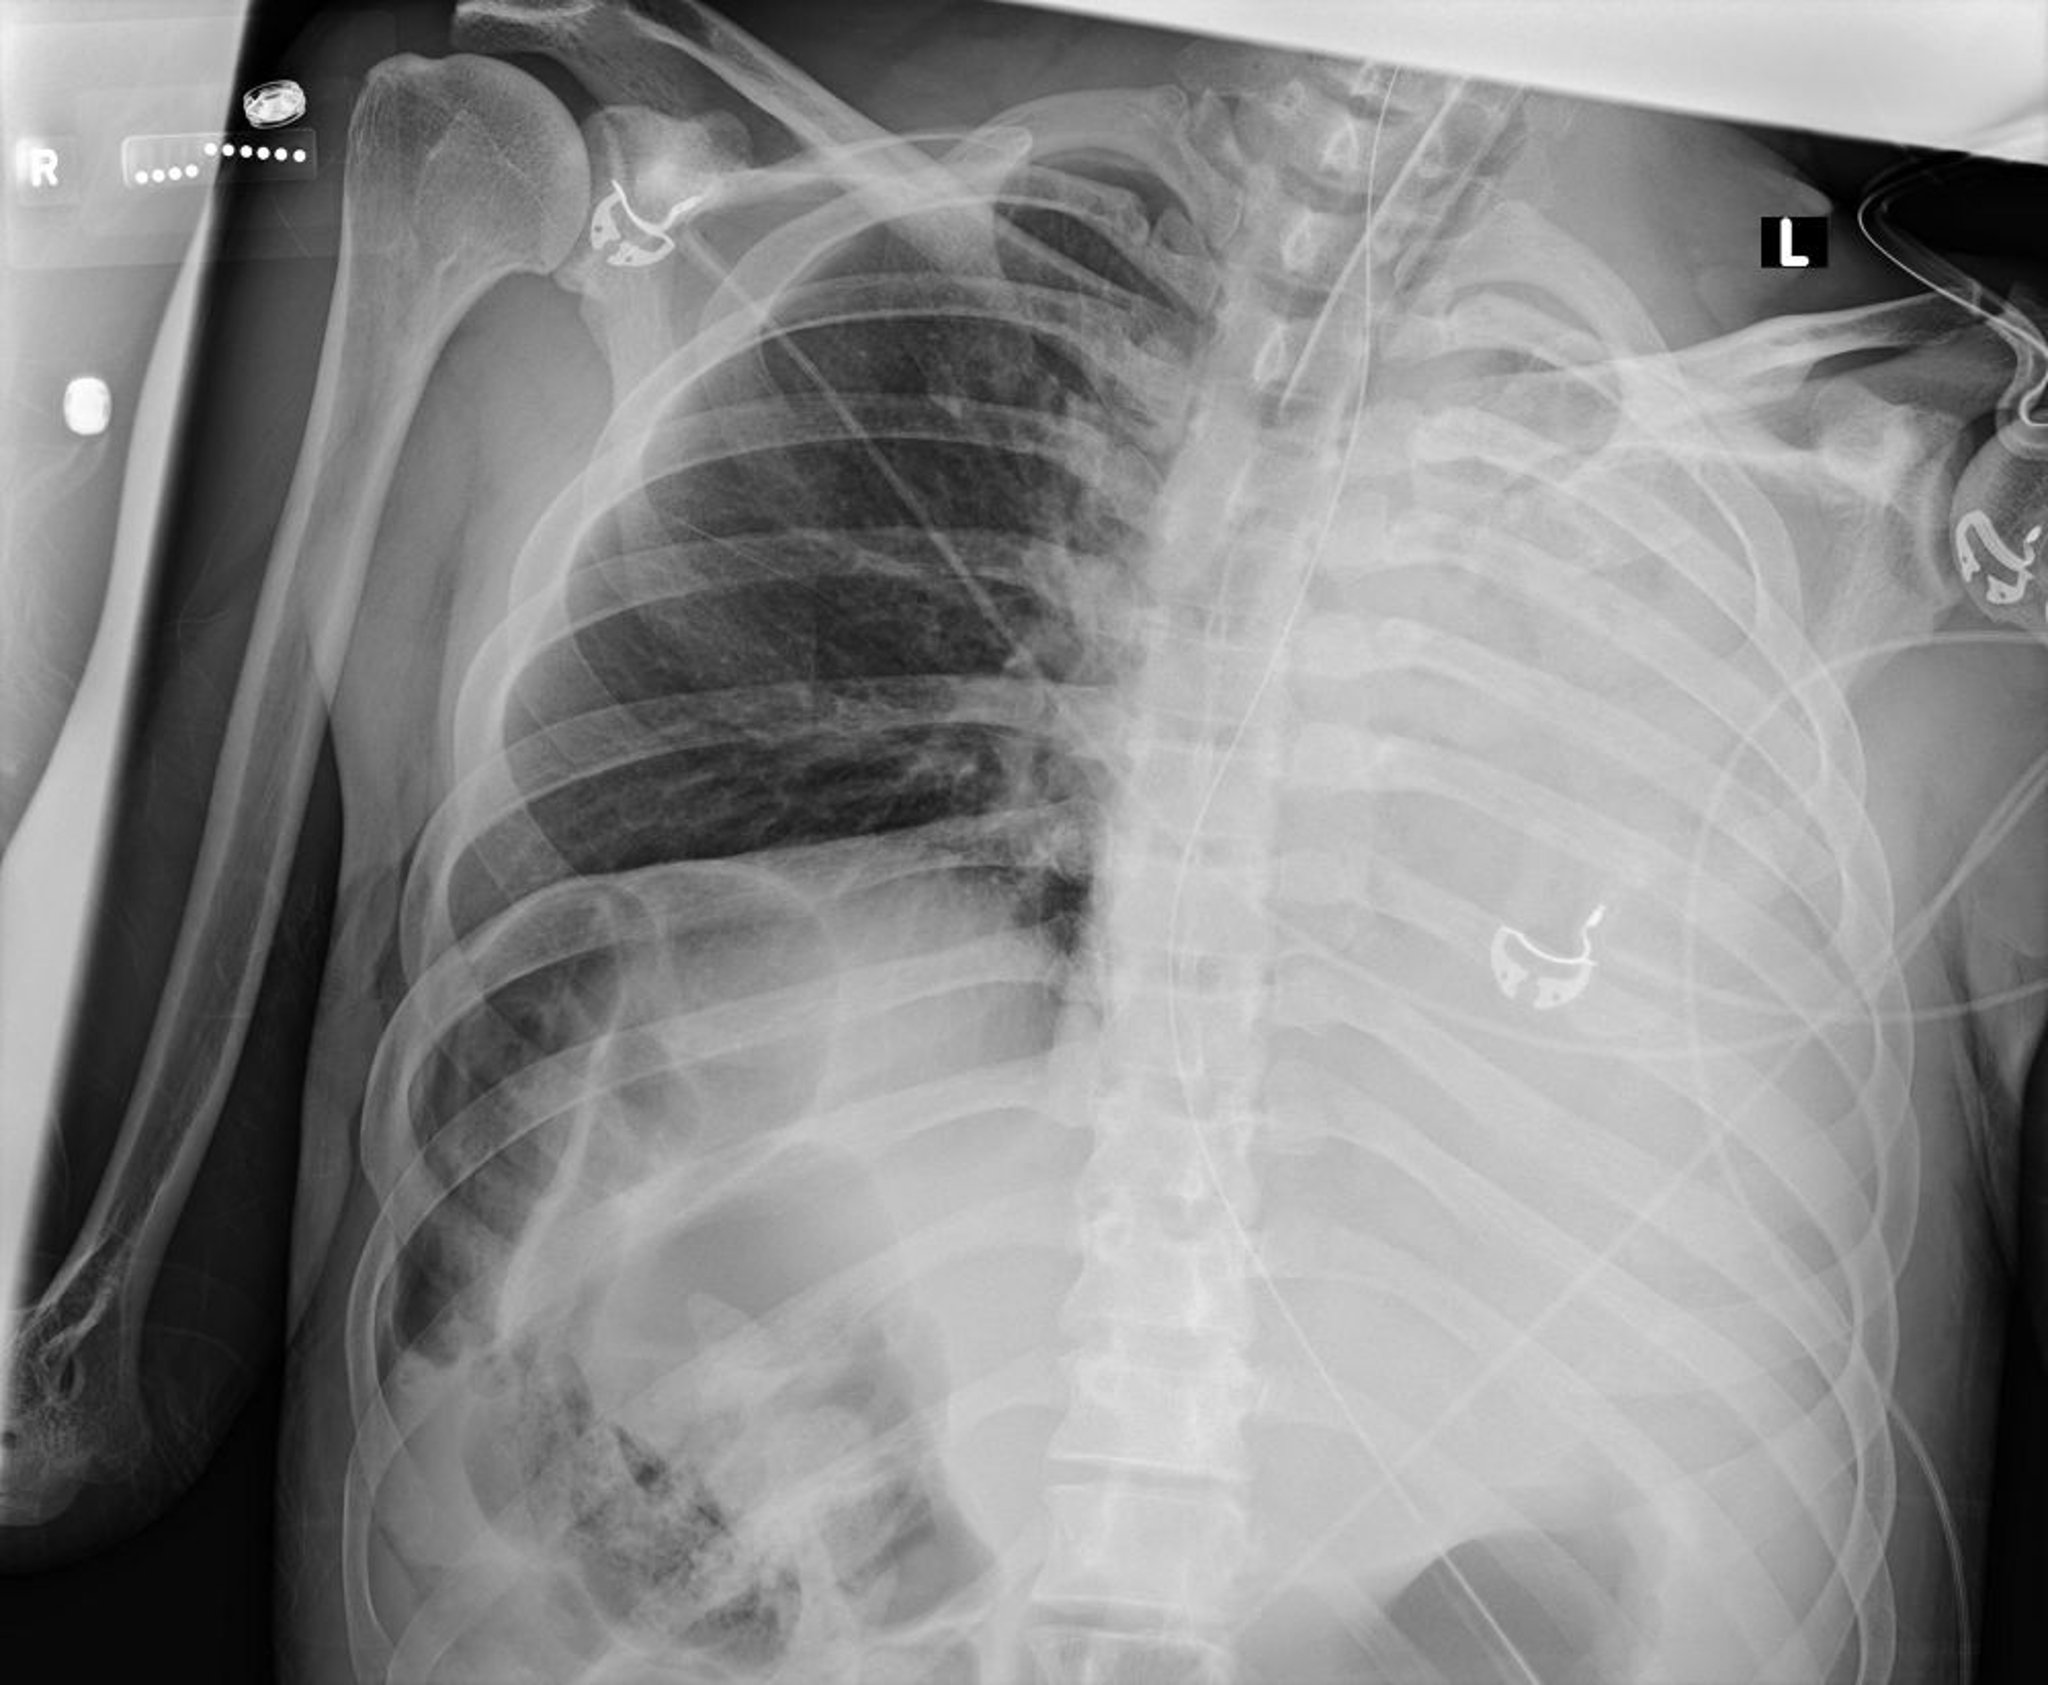

Atélectasie et collapsus du poumon gauche (radiographie)

Cette radiographie thoracique montre un collapsus de tous les lobes du poumon gauche dû à un bouchon de mucus.